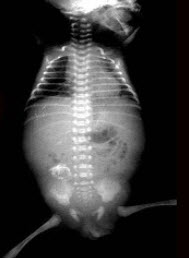

32、单项选择题

男,出生后2天。哭闹不止,腹胀。如图所示,最可能的诊断为()

A.肠套叠

B.肠闭锁

C.胎粪性腹膜炎

D.肠扭转

E.肠狭窄